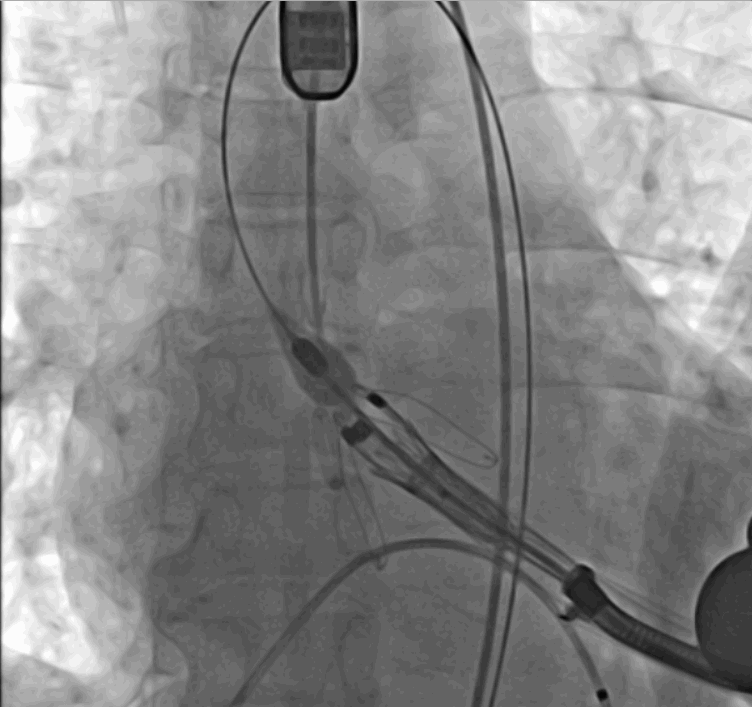

術(shù)中瓣膜釋放過程

手術(shù)采用經(jīng)心尖入路,對患者進行全麻后,在左側(cè)心尖處做3-4cm微創(chuàng)手術(shù)切口,在DSA及超聲引導(dǎo)下手術(shù)順利完成。從導(dǎo)入器械到完成瓣膜置入,僅耗時約10分鐘。術(shù)后即刻主動脈瓣返流程度由術(shù)前大量返流轉(zhuǎn)為消失,患者于導(dǎo)管室拔除氣管插管,次日由ICU轉(zhuǎn)入普通病房。